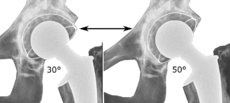

The direction of the acetabular cup influences the range of motion of the leg, and also affects the risk of dislocation.[7] For this purpose, the acetabular inclination and the acetabular anteversion are measurements of cup angulation in the coronal plane and the sagittal plane, respectively.

Acetabular inclination.[78] This parameter is calculated on an anteroposterior radiograph as the angle between a line through the lateral and medial margins of the acetabular cup and the transischial line which is tangential to the inferior margins of the ischium bones.[78]

Acetabular inclination is normally between 30 and 50°.[78] A larger angle increases the risk of dislocation.[7]